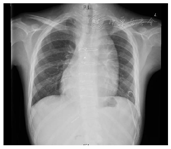

患者入院查体:体温36.4℃,脉搏98次/分,呼吸21次/分,血压147/91 mmHg;SPO2 60%;发育正常,营养中等,无病容,表情自如,神志清楚,自主体位,查体合作。口唇明显青紫,面部青紫,双肺呼吸音清,未闻及明显干湿啰音,心音可,律齐,P2<A2,胸骨左缘2、3、4肋间闻及2-3/6级粗糙的收缩期杂音。腹部平坦,腹壁软,全腹无压痛,无反跳痛、肌紧张反跳痛、肌紧张,肝肋下未触及,胆囊未触及,脾不大,无移动性浊音,双侧肾区无叩痛,肠鸣音正常。双下肢无水肿。四肢末梢青紫,伴杵状指(图1)。

入院后,完善各项术前检查,包括心脏超声(图2),心脏及大血管CT(图3),调整患者营养状况,进行呼吸功能训练并多次进行多学科团队讨论。最后明确术前诊断:先天性心脏病:矫正型大动脉转位,室间隔缺损,肺动脉及其瓣下狭窄,二尖瓣中量返流,体肺侧支循环,间断加速性室性自主心律,室性早搏,房性早搏。